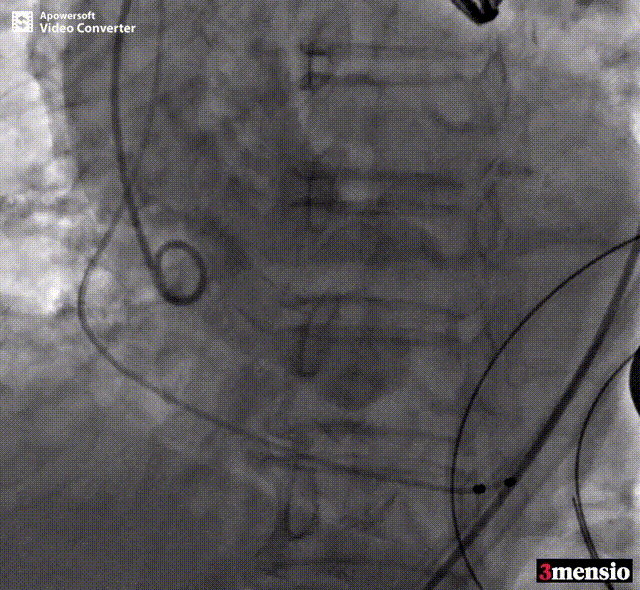

患者全麻后,于左侧心尖3-4cm处进行微创手术切口。在DSA及超声引导下,输送Ken-Valve瓣膜系统进入左心室,边调弯边推送,使得瓣膜在术中始终保持较好的同轴性,从送入输送器到瓣膜释放不足十分钟。术后即刻患者反流消失,于外科杂交手术室拔除气管插管,次日即由ICU转入普通病房。

术中释放定位键后DSA影像图